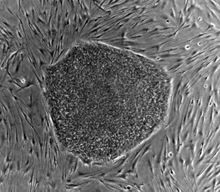

نشرت مجلة( سينتفيك أمريكان ) مؤخرا مقالا مثيرا بعنوان (أول جنين مستنسخ) يدور حول إستنساخ أجنة بشرية في مراحلها المبكرة. وهذه الأجنة تتولد من البويضات بطريقة يطلق عليها الإستنساخ العلاجي Therapeutic cloning. وهذه العملية تتم من خلال تقنية تكنولوجيا الخلية المتطورة Advanced Cell Technology حيث إستخدم العلماء تقنية النقل النووي nuclear transplantation الذي يعرف بالإستنساخ cloning. ويقول العالمانجوس سيبيلي و مايكل كارول إيزيللي بعد تلقيح الخلية المفرغة النواة شاهدا تحت الميكروسكوب كرات من خلايا منقسمة لاتري بالعين المجردة. وهذه تعتبر أول أجنة بشرية أنتجت وأستنسخت في أكتوبر عام 2001. ولما وصلت كل كرة لمرحلة الإنقسام وصل عدد خلاياها 100 خلية بكل كرة جنينية. أطلق عليها بلاستوسستات (خلايا جنينية متحوصلة) blastocysts. وهي عبارة عن أجنة في مراحلها الأولي المبكرة. ويهدف العالمان إستخلاص خلايا جذعية بشرية من هذه الأجنة المبكرة. وزراعتها لتنتج الأعصاب والأعضاء والأنسجة الحيوية. وهذه الخلايا الجذعية البشرية human stem cells ستكون في بنوك لإنتاج الأعضاء وقطع الغيار البشرية. ولسوء الحظ أحد هذه الأجنة في تجربة مثيرة إنقسم لمرحلة ست خلايا وتوقف نموه .لكن هذه الخطوةالرائدة تعتبر فجرا جديدا بالطب والعلاج الإستنساخي . لأن العالمين إستطاعا حث هذه البويضات البشرية كهربائيا للإنقسام دون التلقيح بالحيوانات المنوية وإنتاج كرات (العلقة) من الأجنة بدون النطفة.

فالإستنساخ العلاجي يستهدف إستعمال مادة جينية من خلايا المريض نفسه لإنتاج خلايا جزر البنكرياس لعلاج السكر أو خلايا عصبية لإصلاح العمود الفقري التالف . وهو غير الإستنساخ التكاثري reproductive cloningالذي يستهدف إدخال وزراعة جنين مستنسخ في رحم امرأة لولادة طفل مستنسخ . وهذه التقنية التي تتبع في هذا الإستنساخ التكاثري تمثل مخاطرة للأم الحاضن للجنين. كما تشكل خطورة علي الجنين نفسه . لهذا أكثر علماء الإستنساخ يعارضون فكرة الإستنساخ البشري التكاثري . لكن الإستنساخ العلاجي يجد قبولا لدي كثيرين من العلماء ورجال الدين. لأنه لايقتل أجنة كاملة النمو ولايمس الموروث الجيني للبشر كما خلقه الله أو يتلاعب في مورثاته التي ميزتنا وجعلتنا بشرا. وكان العالمان قد إستشارا علماء الأخلاق والإجتماع لإجراء تجاربهما حتي لايقعا في محاذير دينية أو أخلاقية لإستنساخهما أجنة بشرية.